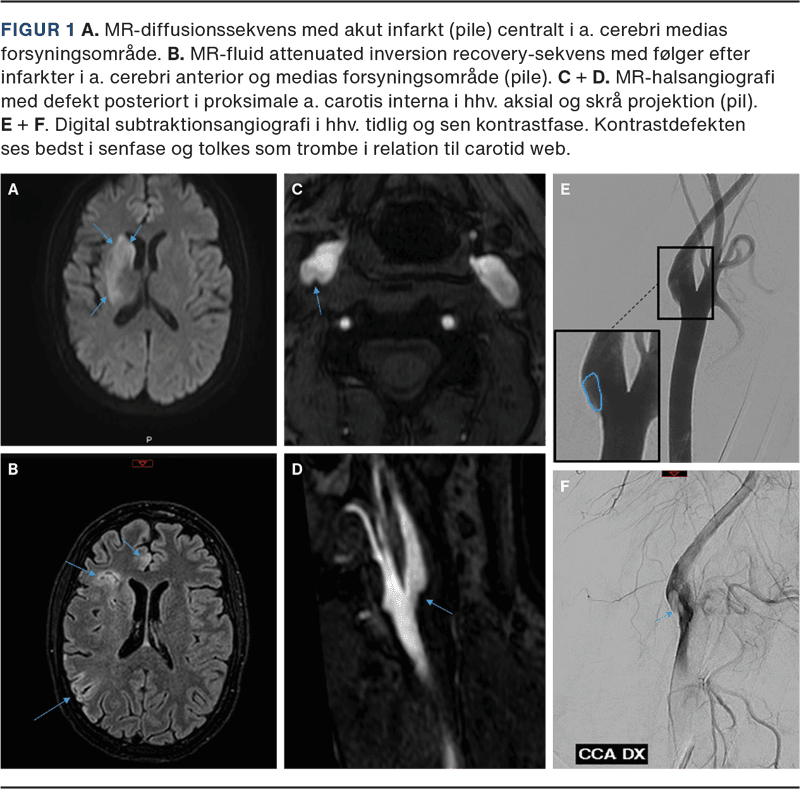

I løbet af den næste måned blev hun indlagt yderligere to gange med varierende venstresidige udfald, herunder central facialisparese, dysartri, visuel neglect, hemiparese og hemihypæstesi. Ved hver indlæggelse påvistes nytilkomne infarkter i det anteriore gebet i højre hemisfære (Figur 1 A + B).

Udredning med MR-skanning af cerebrum (MR-C) med kontrast, lumbalpunktur, helkrops-PET/CT for at udelukke underliggende malignitet og digital subtraktionsangiografi (DSA) kunne ikke forklare de gentagne iskæmiske strokes. Transøsofageal ekkokardiografi påviste et stort persisterende foramen ovale (PFO), og man påbegyndte behandling med dabigatran, idet nye infarkter var opstået trods DAPT. I den næste måned, i ventetiden på PFO-lukning, fik patienten et nyt infarkt i det anteriore gebet i højre hemisfære. Patientens PFO blev lukket, og hun overgik til behandling med clopidogrel. Elleve dage senere fik hun et nyt iskæmisk stroke med venstresidige udfald som tidligere beskrevet. MR-C inkl. angiografi påviste nytilkommen iskæmi i højre hemisfære med distal M1-trombe, og hun fik foretaget trombektomi.

Patienten havde altså nu haft seks iskæmiske strokes fra det anteriore gebet i højre hemisfære på trods af relevant pladehæmmerbehandling, antikoagulationsbehandling og vellykket PFO-lukning. På mistanke om CW udførtes MR-angiografi af halskar på ny, og denne gang rejste sig mistanke om karanomalien proksimalt i højre a. carotis interna (ICA) (Figur 1 C + D). Efterfølgende foretoges DSA forudgået af loading med tabletter clopidogrel og acetylsalicylsyre. DSA’en blev denne gang suppleret med skråoptagelser, som bekræftede fundet, der sås mest tydeligt i den sene kontrastfase [3] (Figur 1 E + F). Der blev anlagt en stent i CW i højre ICA, og patienten fortsatte i DAPT i vanlig vedligeholdelsesdosis.